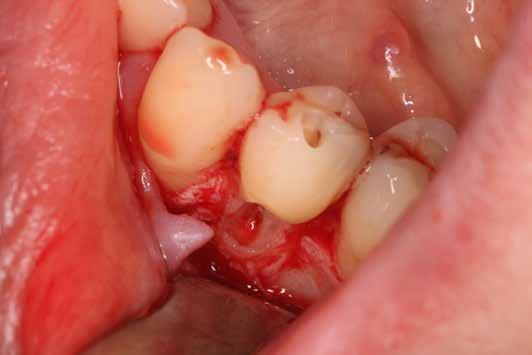

A megfelelő vizuális kontroll és az izolálhatóság kedvéért lebenyt alakítottunk [4. kép]. Így az abszolút izolálás már kivitelezhető volt és kofferdám izolálásban kezeltük a léziót [5. kép]. Mivel az elváltozás nem látható területen helyezkedett el, illetve a kavitás kis kiterjedését figyelembe véve kalcium-szilikát bázisú anyagot választottunk a restauráláshoz (Biodentine, Septodont) [6. kép]. Miután letelt a választott anyagunk kötési ideje (12 perc), zártuk a lebenyt [6. kép]. Páciensünk azóta is panaszmentes, kétéves kontrollon állapota rendben volt [7. és 8. kép].

Az üregben nagy mennyiségű gyulladásos szövetet találtunk, mely eltávolítása után láthatóvá vált a kavitás kiterjedése [13. kép]. A kisőrlő fogakra jellemző tengelyirányú, valamint oldalirányú terhelés kombinációja, valamint a jelentős foganyagveszteség miatt szerettük volna a lehető legjobban megerősíteni a fogat. A terület kofferdám gumilepedővel történő abszolút izolálása után a gyö-

kércsatornát egy guttapercha segítségével kiblokkoltuk, ezzel megelőzve a csatorna obliterálódását [14. kép]. Ezután megfelelő adhezív előkezelést követően kompozit tömőanyaggal restauráltuk az elváltozást (Essentia Universal, GC Europe) [15. kép]. Finírozást és alapos polírozást követően zártuk lebenyünket, majd újabb kofferdám izolálásban elvégeztük a fog gyökérkezelését [16. és 17. kép]. A kezelést követően páciensünk teljesen panaszmentes

volt. Két hónapos kontrollon a fog teljesen ép, az íny tökéletes kitapadását tapasztaltuk [18. és 19. kép]. Szondázási mélység a bukkális oldalon mindenhol 2 mm alatt volt.